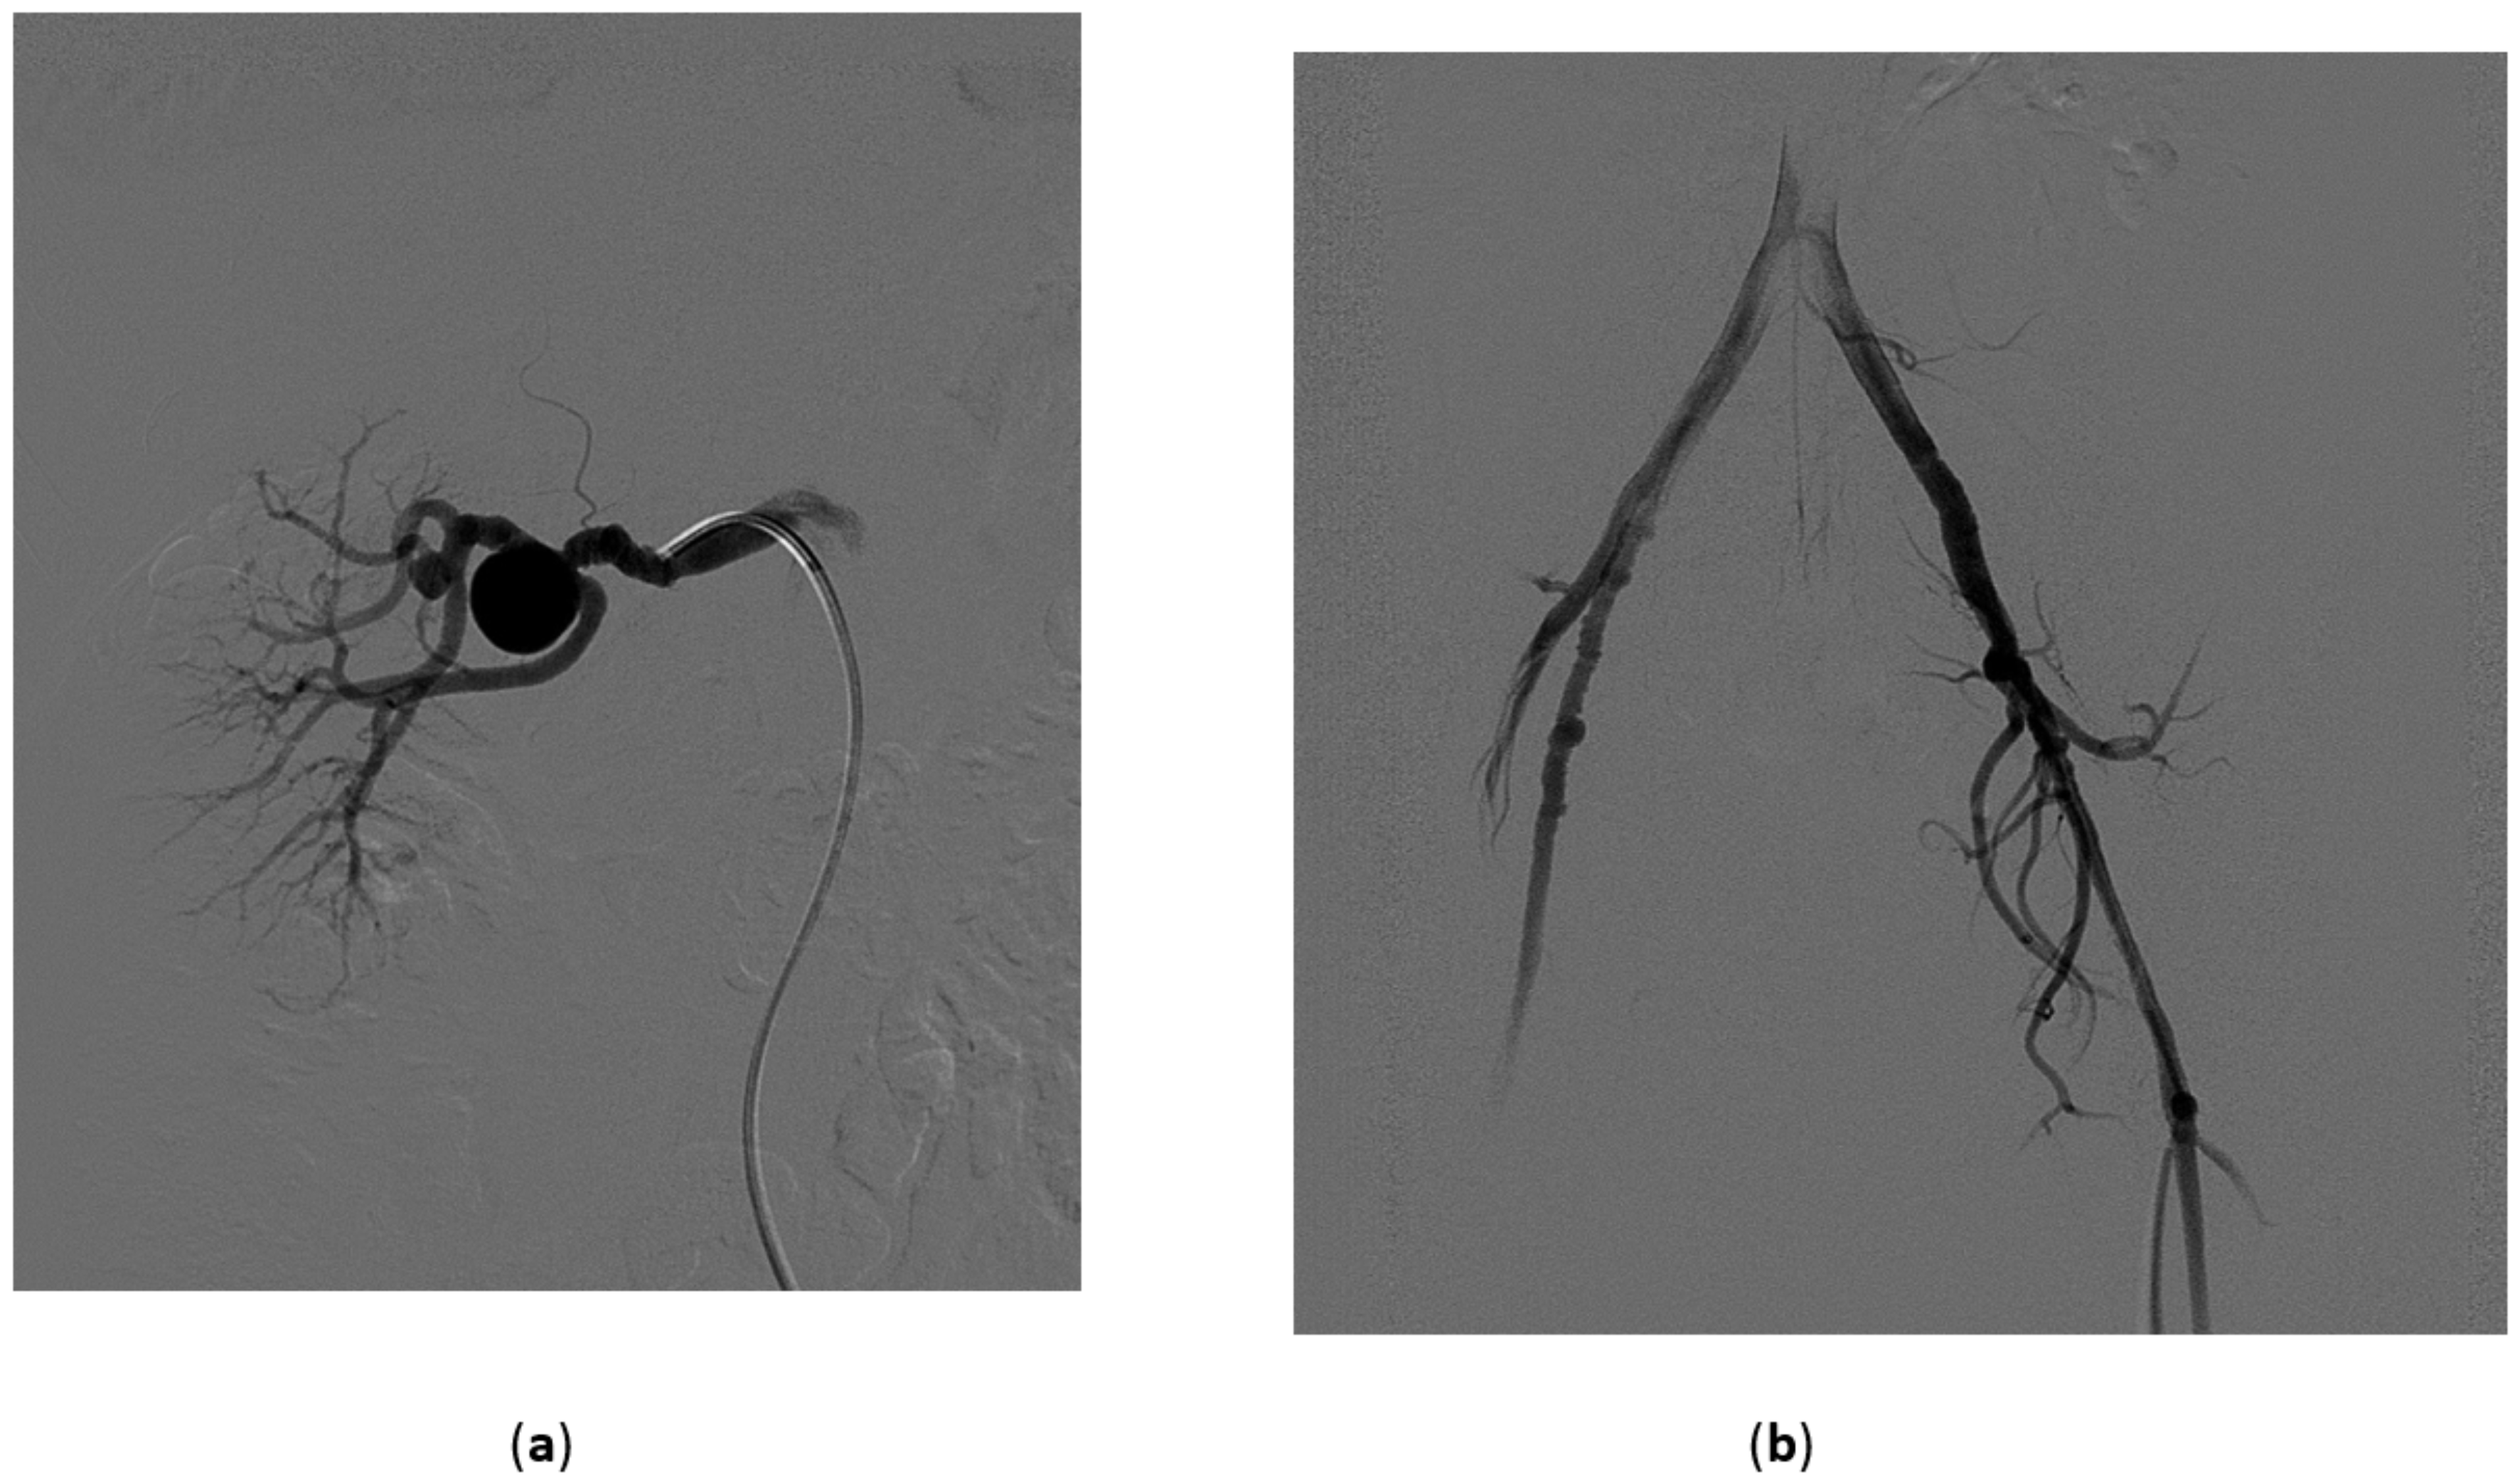

5.1. High-Flow Priapism

5.3. Treatment of High-Flow Priapism